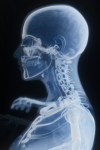

Fuente Fotografía: Elsevier